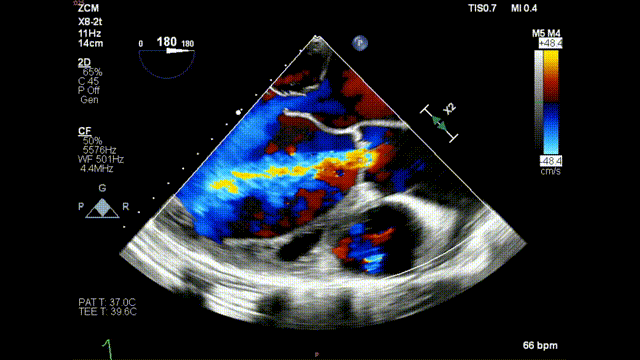

术前食道超声示:

术前食道超声-短轴color

术前食道超声-长轴color

术后食道超声示:

术后食道超声-短轴

术后食道超声-长轴